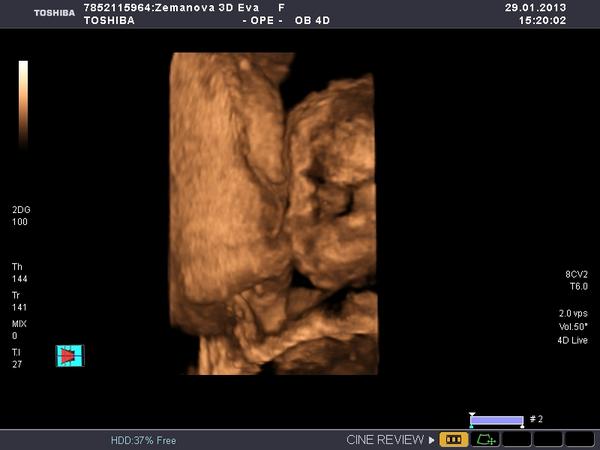

Ráno v 7:30 jsem opustila teplo svého domova a odjela sednout si k počítači a pracovat. Dosedla jsem v 8:10 a do teď u toho počítače dřepim (pár přestávek jsem měla, abych nekecala) a odhaduju, že ještě tak 2 hodiny tu dřepět budu a ráno v osm už mám zase vyzvedávat klienta a jet někam do horoucích pekel. A PAK MI NĚKDO VYSVĚTLETE, JAK TO NAŠI MYSLELI, KDYŽ ŘÍKALI,AŤ SE UČÍM, ABYCH MĚLA HEZKOU PRÁCI A MOHLA SI UŽÍVAT!?! jediný co mě s tím smiřuje, že můj hodný muž přijel a pomáhá mi, abychom to měli rychleji a má "prolhaná" matka je ve vedlejší kanceláři a dělá taky... Jestli se ve čtvrtek ukáže, že čekáme děvčátko, tak ho vychovám, aby se dobře vdalo a může být klidně úplně blbá.... 😀